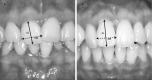

Results: The prevalence of a distinguishable scar remaining at least 1 year after miniscrew removal was 44.6%. Patients with flat gingiva showed a significantly higher prevalence of soft tissue scar formation than did those with pronounced scalloped gingiva (P < .05). Maxillary buccal removal sites showed a significantly higher prevalence of soft tissue scar formation than did those in the mandible or palatal slope (P < .05). Miniscrew sites at the alveolar mucosa showed a significantly lower prevalence of soft tissue scar formation than did those in the mucogingival junction or the attached gingiva (P < .01).

Conclusion: The prevalence of distinguishable scarring after miniscrew removal was fairly high. On the basis of our results, patients with flat gingiva and buccal interdental gingival insertion sites are more susceptible to scar formation.